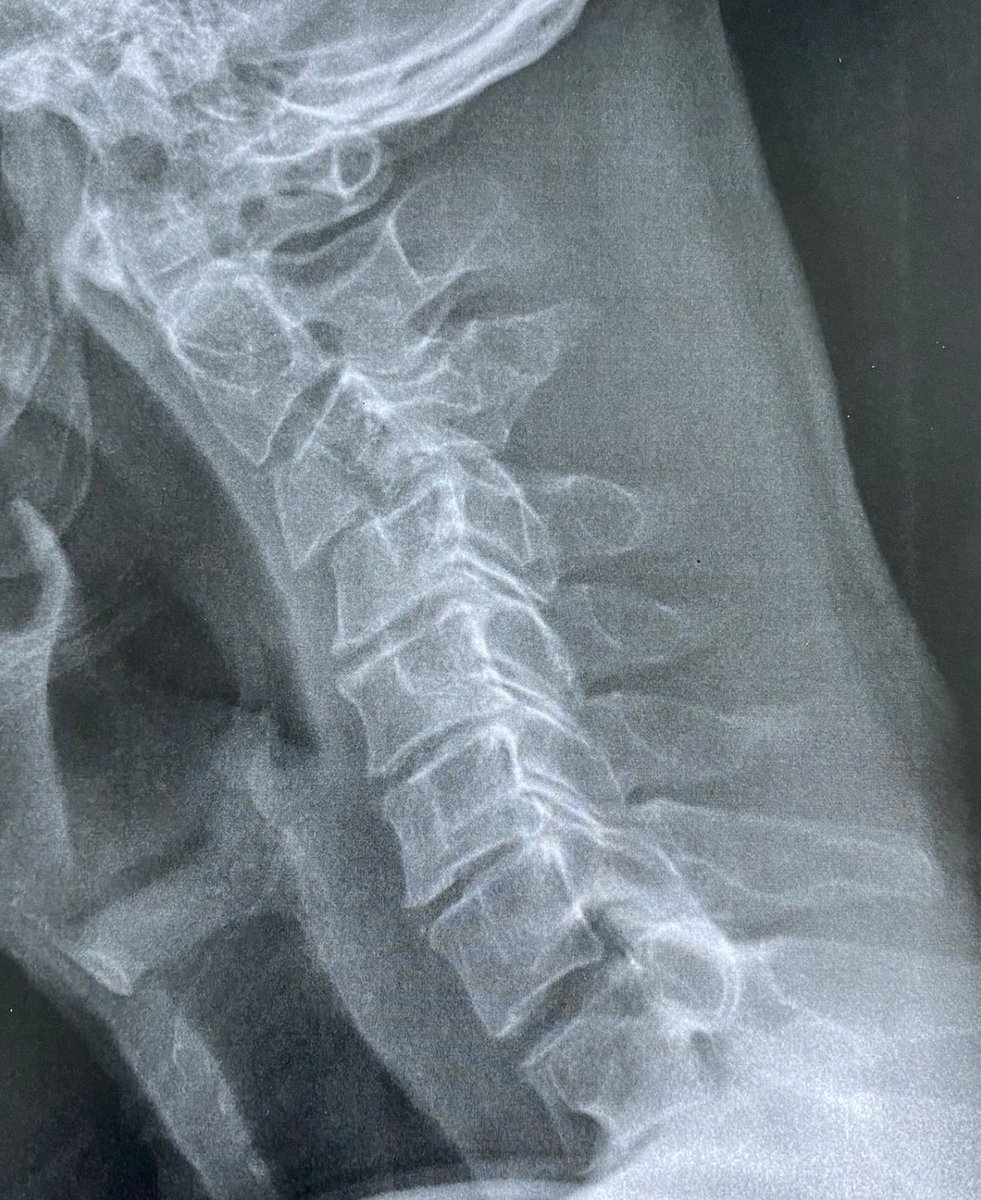

Je vous l'avais pas montré celle-ci, je la gardais dans mon téléphone le temps de m'assurer que l'histoire se finisse bien. Voici une radio d'une patiente du cabinet. Venue consulter sur insistance de sa fille car c'est pas normal d'avoir mal au cou après avoir vu 2x un ostéo.

1/ Image

Ho, je vous rassure, c'est pas l'ostéopathe qui a fait ça. C'est la chute deux jours avant de le voir. Chute sur la tête. Mal de cou, hop, sans réfléchir, va voir SON ostéo habituel. Le bon ostéo réputé et super sympa, qui MANIPULE sans broncher le cou.

Et pas une fois, mais 2 FOIS car la douleur persiste. A aucun moment alors qu'il savait que c'était suite à une chute il se dit "hum, ça s'rait bien une radio, quan' meme". Bha vi, regardez la gueule de la radio : fractures, courbure inversée, diastasys, etc.